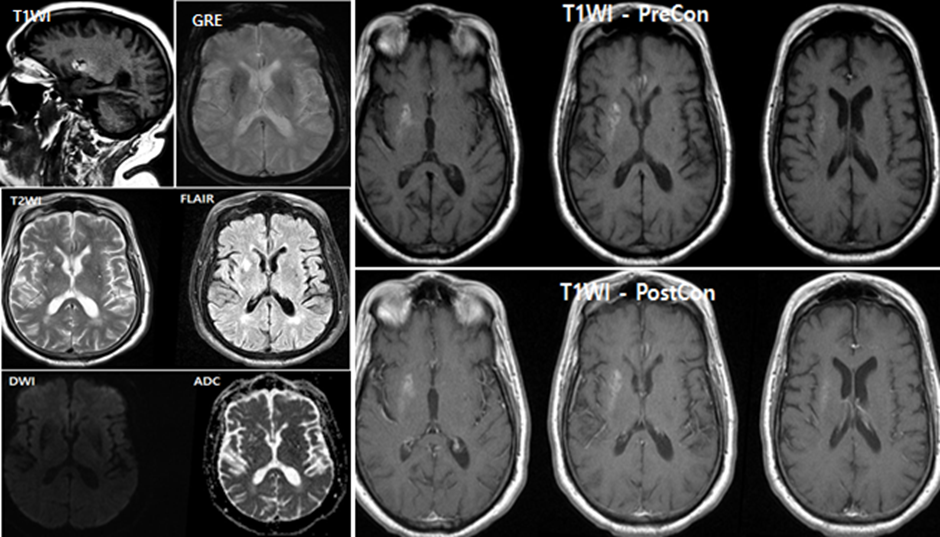

Additional Clinical History and MRI Imaging

1. The patient has a history of poorly controlled chronic diabetes mellitus.

2. Brain MRI was subsequently performed for further evaluation.

Quiz 2:

1. Is there abnormal contrast enhancement?

(1) True

(2) False

Explanation: No abnormal contrast enhancement is seen. In nonketotic hyperglycemic hemichorea, contrast enhancement is typically absent on MRI.

2. Is diffusion restricted?

Explanation: Diffusion-weighted imaging does not show restriction, helping distinguish this entity from acute ischemic stroke.

3. Is there hemorrhage?

Explanation: Despite high signal intensity in the basal ganglia on T1-weighted images or hyperdensity on CT, there is no evidence of true hemorrhage or associated mass effect.

MRI Findings

• T1-weighted images: High signal intensity in the basal ganglia, especially the caudate nucleus and putamen (with or without globus pallidus involvement).

• T2/FLAIR: Often normal or only mildly hyperintense—less sensitive.

• No contrast enhancement or restricted diffusion.

• Susceptibility imaging (SWI/GRE): Usually normal in early stages; may show low signal intensity later due to metal deposition (e.g., manganese or iron).

Imaging Summary

• Side: Contralateral to the clinical symptoms.

• CT: May show hyperdensity in the basal ganglia, often interpreted initially as hemorrhage.

• MRI:

• T1 hyperintensity in the caudate and putamen is characteristic.

• T2/FLAIR changes are subtle.

• No enhancement or diffusion restriction.

• SWI/GRE: Normal early; may show low signal later due to mineral deposition.